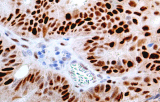

- Assegnazione del lignaggio & principali diagnosi differenziali: Fenotipizzazione cellule B vs cellule T (es. CD20 vs CD3), supportata da fattori di trascrizione nucleari delle cellule B come PAX5 quando i marcatori pan-B sono deboli/assenti.

- Linfoma di Hodgkin classico: le cellule tumorali sono tipicamente CD30+ e spesso CD15+, con PAX5 debole e CD20 negativo nelle grandi cellule tumorali.